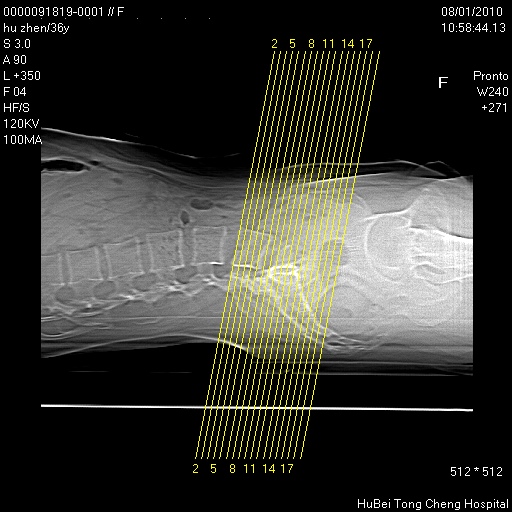

患者 女,36岁。右侧腰腿痛半月余。腰骶椎mr平扫偶然发现骶椎异常信号。

临床诊断:1)腰椎间盘突出症。2)骶椎肿瘤性病变?

骶椎ct平扫(层厚、层距均为5mm),图像如下: